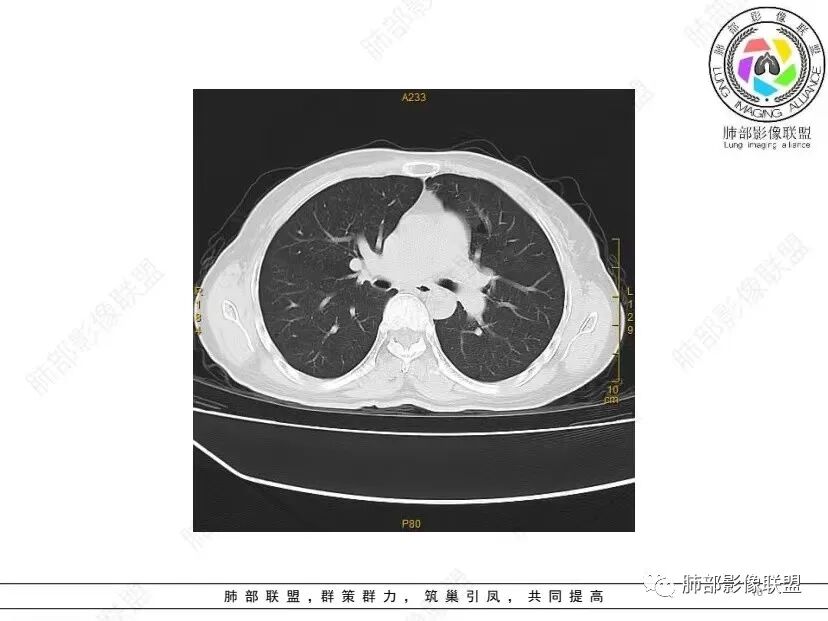

中年女性,否认肿瘤病史,双肺多发气囊,中下肺相对多发,考虑LIP,鉴别BHD综合征。

秦化君: 晨读 双肺不均匀散在多发囊状影,大小不等,部分囊形态欠规整,壁薄均匀,部分囊胸膜下平行。双肺少许斑片状磨玻璃影,边缘模糊。考虑BHD综合征。鉴别PCP,LIP。

红日初升: 中年女性,双肺多发气囊,背景干净,大小不一,下肺韧带旁较大,考虑BHD,鉴别LIP、LAM

玫: 晨读:女,49岁,双肺散在多发囊性病灶影,薄壁,部分层面病灶形态欠规整,右肺下叶少许磨玻璃影,边缘模糊,考虑LIP,鉴别BHD。

宇宙: 中年女性,两肺多发大小不等薄壁囊状影,两肺纵膈胸膜下分布明显,考虑BHD,鉴别LAM

放射线 (王秀仙): 双肺多发囊状影,大小不等,部分囊壁呈磨玻璃样,另双肺见斑片状磨玻璃影,边缘模糊。女性,考虑LIP,鉴别BHD

段建民: 双肺多发囊状影,多成圆形或三角形,囊壁薄且均匀,正常肺野内透过度尚可。双肺多发囊状影的鉴别,中心肺气肿,间隔旁肺气肿,PJP,支气管扩张,囊肿,支气管肺发育异常;LAM LIP PLCH BHD;囊腔腺癌,转移瘤,血播金葡菌……

本病例首先考虑BHD。

小飞: 晨读,中年女性,病史保密,两肺散在薄壁囊腔,肺底较多,部分较大,双肺少许磨玻璃密度影,考虑LIP

良孑: 两肺多发含气囊腔,大小不等,囊周见血管伴行,首选BHD,建议查双肾情况,鉴别Lam

这个病例目前影像特点,多囊,囊主要位于下肺,胸膜下及小叶核心为主

伴随少许索条,而且这些病灶与囊不一定有相关性

囊的分布,PLCH基本可以排除

囊壁薄且均匀,光滑,形态规则,基本除外恶性

单纯囊,无斑片及其他实性病灶,感染不支持,可能的是:LAM、BHD、LIP

从囊的分布、大小,BHD可能性可能大一些,但是LIP、LAM都可以这样表现,具体诊断应该是这三种之一,影像缩小到这里我觉得就差不多了,结合临床考虑就行,不支持靠影像强下结论。